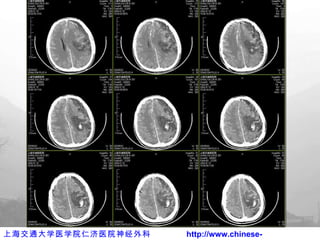

伤后  2h CT

术后 CT 复查

术后出院前 CT

术后 3D CT